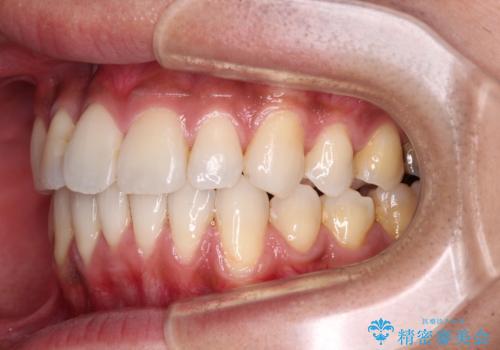

上顎の狭い歯列をインビザラインで拡大

- 上下前歯の叢生を気にして来院された患者様です。

奥歯はクロスバイトとなっているので上顎は側方拡大を行いつつ、上下全体の叢生をインビザラインにより改善することとしました。